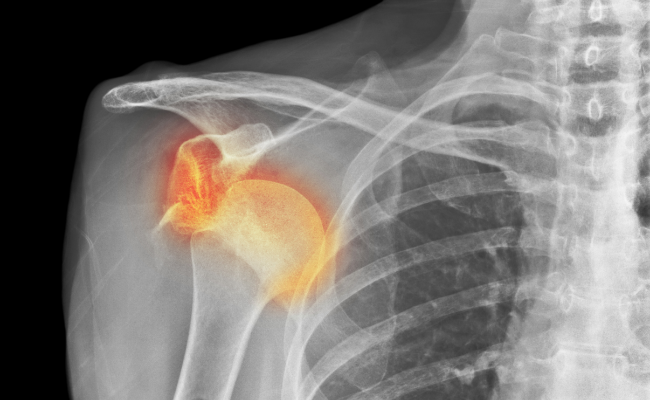

엘보우(테니스 엘보, 골프 엘보), 어깨 회전근개 손상, 관절와순 파열

탈구

스포츠 활동이나 일상생활에서 발생하며 염좌의 2-3단계에 해당되는 경우로

관절면이 어긋나면서 인대손상, 관절낭손상, 연골손상이 함께 발생합니다.

어깨, 손목, 손가락, 발목, 발가락 등에 탈구가 잘 발생합니다.